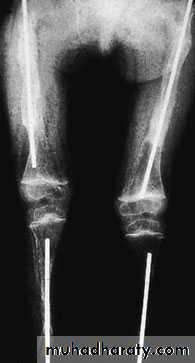

Long-bone deformities are common, these may require operative correction, usually by 4 or 5 years of age. osteotomies are performed and the bone fragments are then realigned on a straight intra medullary

rod; the same effect can be achieved by closed osteoclasis.

The problem of the bone outgrowing the rod has

been addressed by using telescoping nails; however,

these carry a fairly high complication rate.